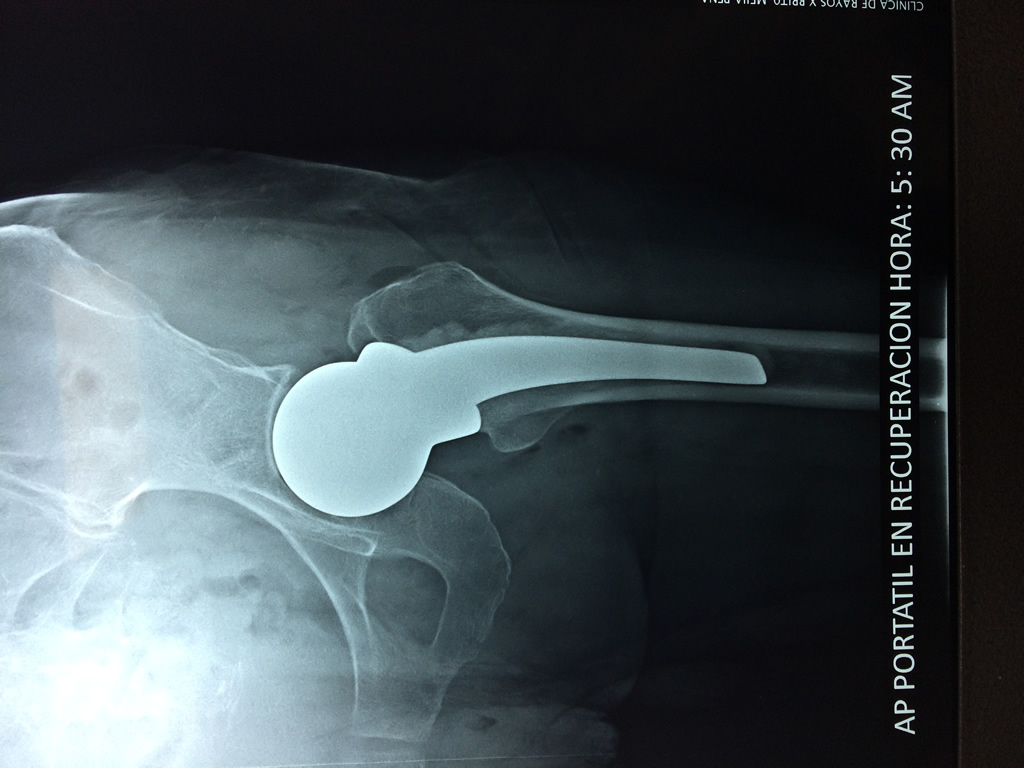

A menudo se recomienda la cirugía para reparar la fractura debido a dichos riesgos.